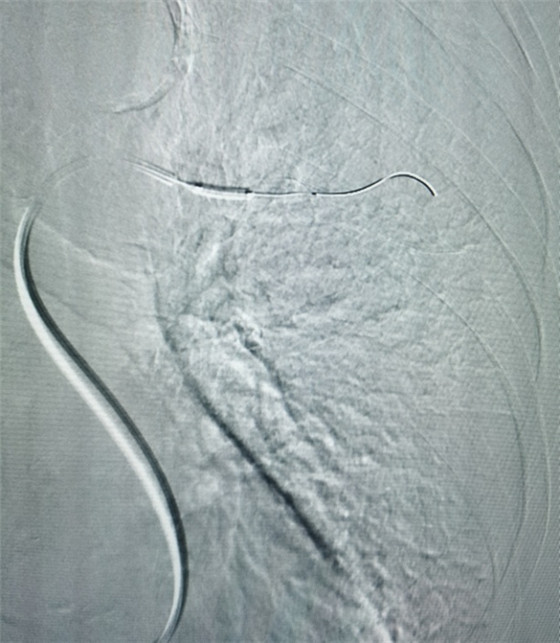

經(jīng)皮肺動脈栓塞導管碎栓溶栓術(shù)

經(jīng)綜合評估并與家屬充分溝通后,局麻下行肺動脈造影,提示左肺動脈主干及左肺下葉動脈閉塞,立即予以經(jīng)皮肺動脈栓塞導管介入碎栓溶栓術(shù)。在心內(nèi)科韋鋒主任、郭良玉主治醫(yī)師及成婷護師的默契配合下,爭分奪秒順利完成手術(shù)。術(shù)后即刻復查肺動脈造影示左肺動脈主干及左肺下葉動脈恢復血流,生命體征穩(wěn)定,指脈氧恢復至100%。經(jīng)過精心治療與護理,目前患者已康復出院。